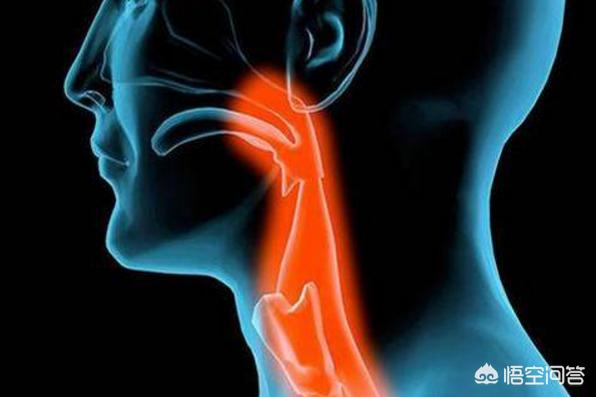

第四に、咽頭炎などの上気道疾患の患者である。このような呼吸器疾患によるドライマウスは、喫煙が好きで、霞のような空気の質の悪い環境に住んでいる場合など、さらに深刻になる。

夜寝ているときに口が渇くという症状が比較的短期間に現れた場合は、咽頭炎、喉頭炎の可能性を考える必要があります。また、発汗や排尿が多くなり、水分が多く失われることによっても起こります。

4.呼吸器疾患。慢性咽頭炎や扁桃腺炎の患者もドライマウスになりやすい。

3.呼吸器疾患におけるドライマウス:風邪、鼻炎、副鼻腔炎、その他の呼吸器系に罹患すると、鼻の通りが悪くなり、呼吸のために過度に口を開ける必要があるため、口の中の水分が蒸発し、口が乾く。

口の中が乾いている状態が長く続くと、少し不快に感じることがある。のどの痛みそして、口の中に何か入っていて、それが取れないんだ。ほてりさらに症状が重い場合は、次のようなこともある。嚥下への影響続く篦太い和スピーチ問題なのは、一部の患者もこのような経験をすることである。鼻腔の乾燥。

タイプ5:咽頭炎およびその他の呼吸器疾患

咽頭炎などの上気道疾患に悩まされ、タバコを吸うのが好きで、霞の中に住んでいるなど、空気の質が比較的悪い環境では、ドライマウスによる呼吸器疾患はより深刻になります。